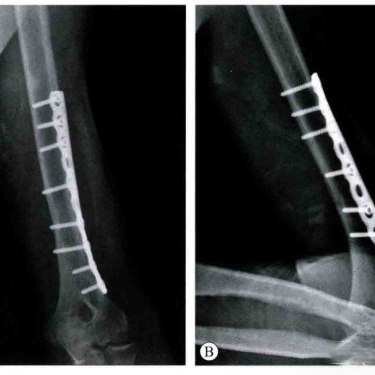

Plates and screws are often used to fix broken bones. Plates are thin metal strips. Doctors attach them to your bone with screws. These implants hold the bone together so it heals straight. Locking plates give extra support for hard breaks or weak bones. Patella Claw and special plates for the ankle and heel help with tough injuries.

Locking plates help bones heal better and give strong support. They stop the bone from moving and help you heal faster.

Locking plates are good for displaced and compound fractures.